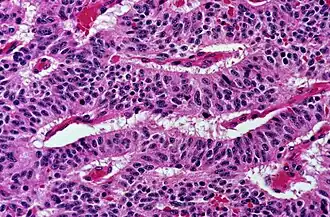

This can be done to slides processed by the chemical fixation or frozen section slides. To see the tissue under a microscope, the sections are stained with one or more pigments. The aim of staining is to reveal cellular components; counterstains are used to provide contrast.

The most commonly used stain in histology is a combination of hematoxylin and eosin (often abbreviated H&E). Hematoxylin is used to stain nuclei blue, while eosin stains the cytoplasm and the extracellular connective tissue matrix of most cells pink. There are hundreds of various other techniques which have been used to selectively stain cells. Other compounds used to color tissue sections include safranin, Oil Red O, congo red, silver salts and artificial dyes. Histochemistry refers to the science of using chemical reactions between laboratory chemicals and components within tissue. A commonly performed histochemical technique is the Perls' Prussian blue reaction, used to demonstrate iron deposits in diseases like Hemochromatosis.[2]

Nests: islands of cells of similar type. -

Solid: More or less the same cell type throughout, with no spaces between, and no other particular pattern. -